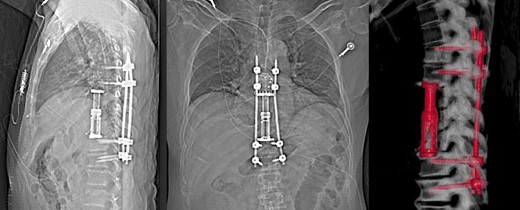

In order to treat the ongoing infection he agreed to undergo aggressive surgical debridement. He underwent open thoracotomy, T8–T10 vertebrectomy, reconstruction with expandable cage and posterior percutaneous pedicle screw fixation of T6–T12 (Nuvasive, San Diego, CA). Surgery was undertaken 5 months after initial presentation and 3 months after initiation of antibiotic therapy.

At time of manuscript patient is 10 month post-surgery, he remains on antibiotic therapy (15 months of continuous treatment) with low dose tigecycline, bedaquiline, clofazimine and cefoxitin, which are well tolerated. Imaging of the spine at 3 months postoperatively shows early signs of bony fusion, preservation of alignment with no hardware complications (Fig. 4), without progression of infection. Patient remains free of neurological deficit and is ambulating normally without back pain.

X-ray and 3D reconstruction following non contrast CT thoracic spine, showing final hardware position and spinal alignment after T8–T10 vertebrectomy, reconstruction with expandable cage and percutaneous pedicle screw fixation of T6–T12 (Nuvasive, San Diego, CA).